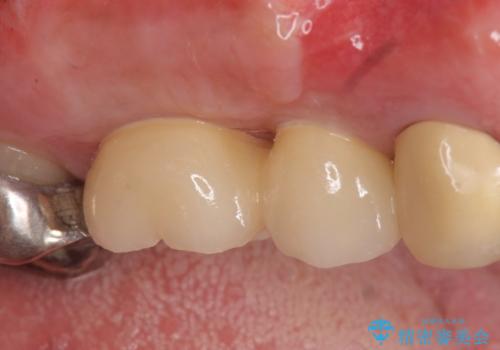

- 右上のブリッジでものを咬むと違和感があり、歯茎に膿の出口もできているので診て欲しいといらっしゃった方の症例です。

右上の567ブリッジを外したところ、右上5は歯根破折により保存不可能だったため、右上56部にインプラントを埋入し欠損補綴を行いました。

今回用いたオールセラミッククラウンはジルコニアフレームという白い素材の上にセラミックを盛っているため、審美性が非常に高いのが特徴です。

また、ジルコニアは人工ダイヤモンドの材料にも使われているほど高い強度を持っており、そのためオールセラミッククラウンは審美性だけでなく、奥歯やブリッジの補綴も可能とするクラウンです。